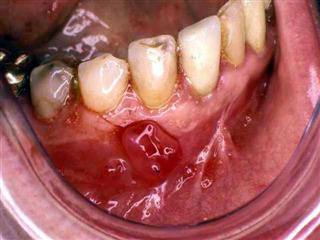

En décembre 1995, ce même patient vient consulter pour une hyperplasie gingivale entre 46 et 45, masse bourgeonnante sensible au contact. Il y a un tassement alimentaire entre ces deux dents du fait d’une carie mésiale de la dent de 6 ans. La biopsie confirme la présence d’une épulis inflammatoire, sans éléments suspects. L’exérèses est pratiquée. Ainsi ce jeune patient a présenté à 13 ans d’intervalle deux tumeurs bénignes de la cavité buccale, pourtant assez rares, surtout le pulpome. Peut-on, dans ce cas, occulter le rôle d’un « terrain » prédisposant ? Car toutes les irritations gingivales ne se terminent pas par une épulis. Sur le plan morphologique, ce jeune patient est manifestement « carbonique ».

Nous avons vu une épulis pédiculée située au niveau de 24-25 disparaître en l’espace d’environ 4 mois avec NATRUM SULFURICUM et THUYA chez une patiente quadragénaire manifestement sycotique à la phase hydrogénoïde. Mais nous avons subi un échec dans le traitement d’une épulis plus bourgeonnante et non pédiculée autour de 11-12 chez une jeune femme de 25 ans de morphologie dystrophique.